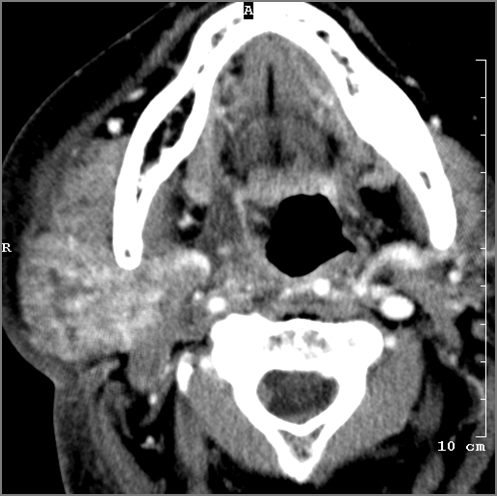

52-year old male with fever, dysphagia and possible aggressive pharyngitis or other infrahyoid neck infections involving the infra hyoid deep neck.Exam

There is general or localized soft tissue swelling of the superficial or deep neck soft tissues. |

There is edema/abscess tonsillar or otherwise or likely suppurative retropharyngeal adenitis involving the oropharynx or adjacent deep tissue spaces. |

There is edema/abscess arising from the hypopharynx, larynx, thyroid gland or trachea. |

There is edema/abscess within the adjacent deep neck, and/or retropharyngeal space. |

Severe pharyngitis with no evidence of abscess